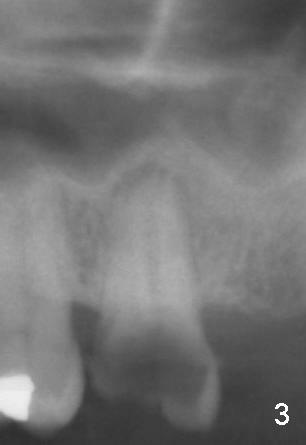

A 52-year-old black man fails to return to finish root canal therapy for the tooth #15; ultimately it is non-salvageable (Fig.1-3).  The tooth has 3 basically fused roots (Fig.4 black (buccal) and red (palatal) outlines), above which is the sinus septum (*).  By inserting an immediate implant into the sinus septum, primary stability should be high (Fig.5 vs. 6).